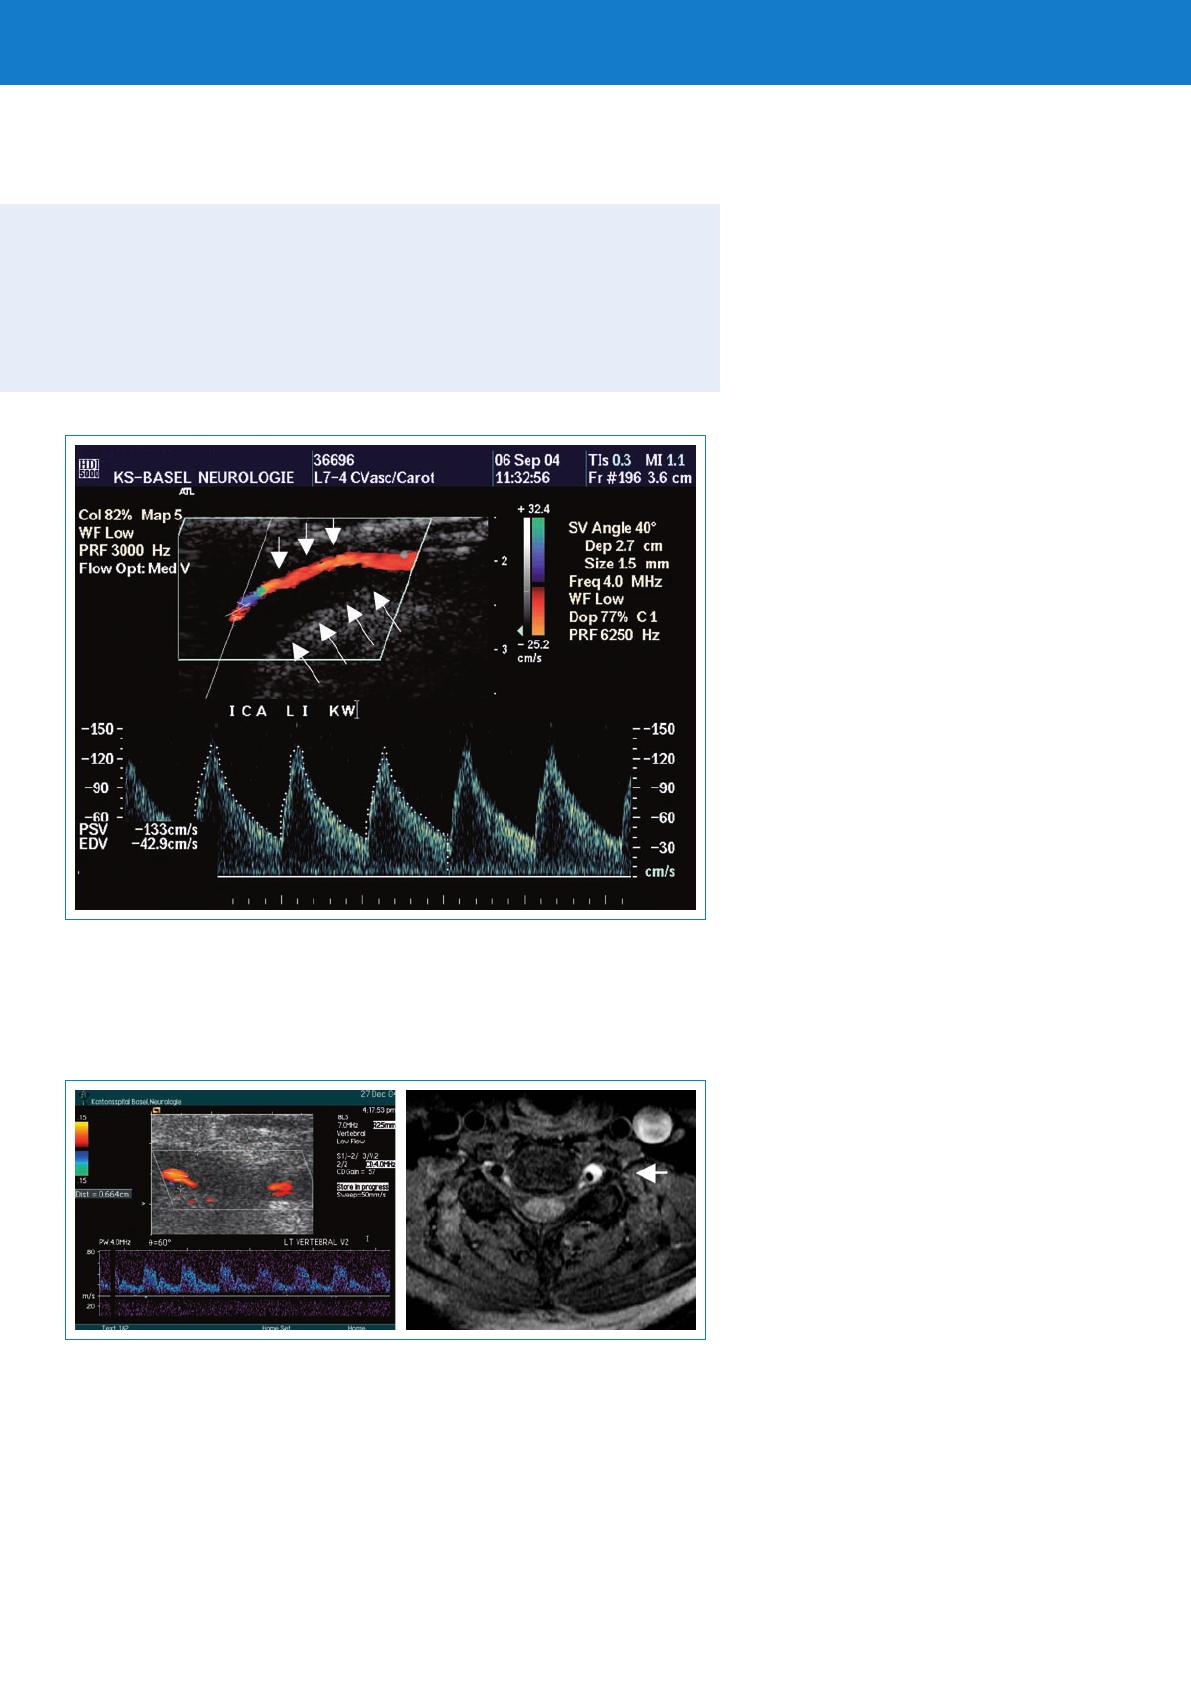

Signaux d’embolie àl’échographie (HITS) malgré double antiagrégation plaquettaire

Occlusion ou pseudo-occlusion de l’artère disséquée

Thrombus flottant dans l’artère disséquée